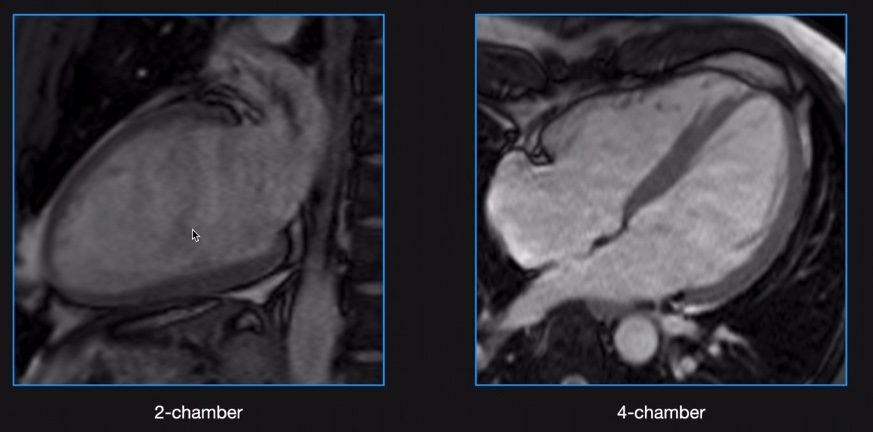

Vues 2 Cavités et 4 Cavités

Vue Ciné 4 Cavités

Vue Ciné 2 Cavités